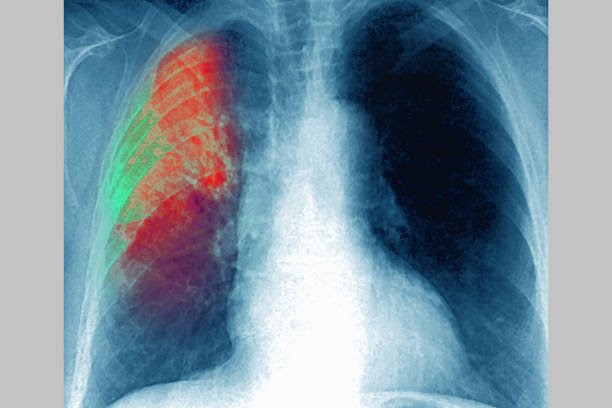

• الرئتين (التهاب رئوي حاد)

هذه العدوى ليست بسيطة: منظمة الصحة العالمية تعتبر المكورات الرئوية أحد أهم أسباب الالتهاب الرئوي القاتل عند الأطفال حول العالم.